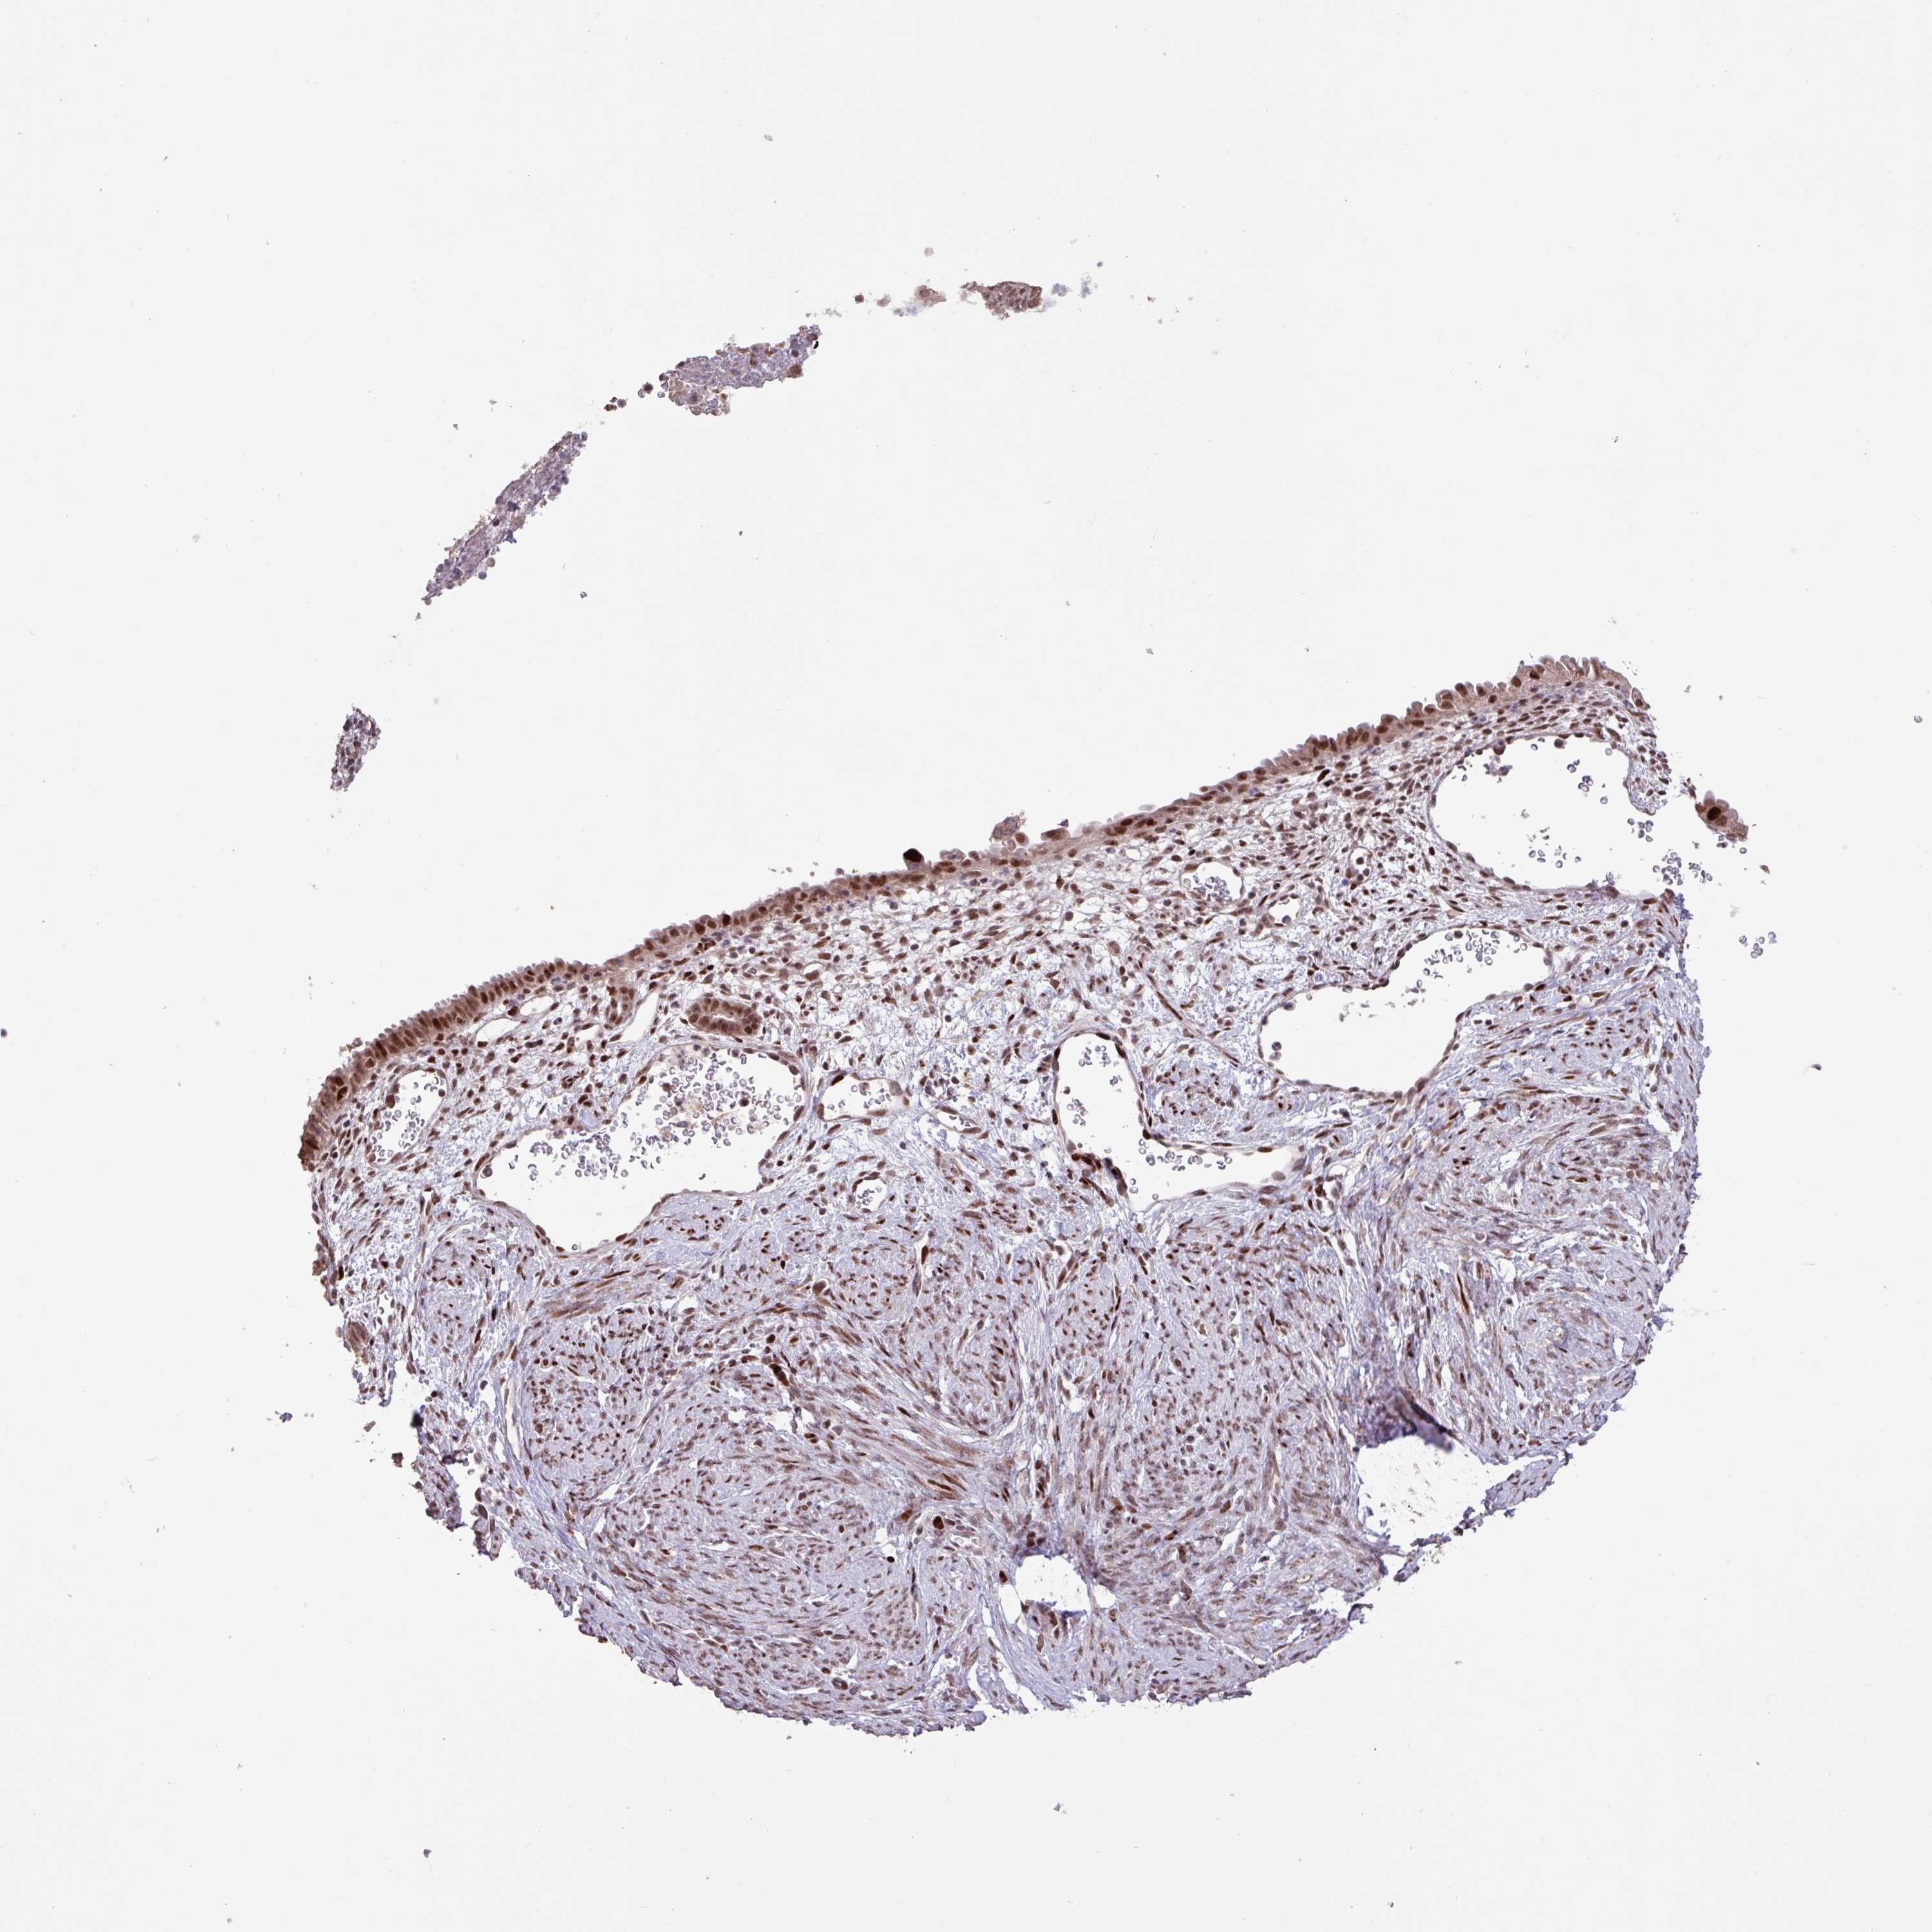

ENDOMETRIAL CANCER - Protein expressioni

A mouse-over function shows sample information and annotation data. Click on an image to view it in a full screen mode. Samples can be filtered based on level of antibody staining by selecting one or several of the following categories: high, medium, low and not detected. The assay and annotation is described here.

Note that samples used for immunohistochemistry by the Human Protein Atlas do not correspond to samples in the TCGA dataset.

Antibody stainingi

Antibody staining in the annotated cell types in the current human tissue is reported as not detected, low, medium, or high, based on conventional immunohistochemistry profiling in selected tissues. This score is based on the combination of the staining intensity and fraction of stained cells.

Each image is clickable and will lead to virtual microscopy that enables deeper exploration of all samples and also displays staining intensity scores, fraction scores and subcellular localization as well as patient and tissue information for each sample.

Antibody HPA053153

Staining

High

Medium

Low

Not detected

Intensity

Strong

Moderate

Weak

Negative

Quantity

>75%

75%-25%

<25%

None

Location

Nuclear

Cytoplasmic/membranous

Cytoplasmic/membranous,nuclear

Adenocarcinoma, NOS